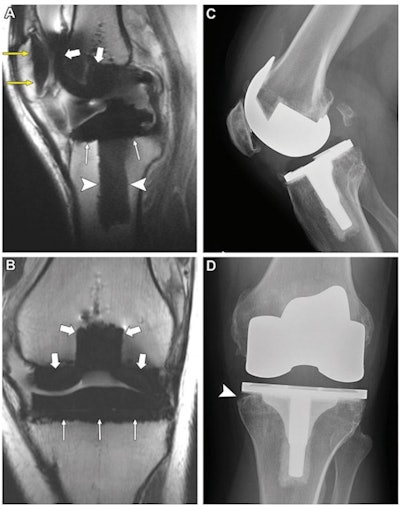

Patients were imaged with both MRI and x-ray, and of the total number of knees, 52.6% had at least one loose component, the team noted. The researchers assessed the type of the interface between the knee replacement component and bone (normal, fibrous membrane, fluid, or osteolysis), the percentage integration of this connection (less than 33%, 33% to 66%, or more than 66%), and the presence of any bone marrow edema; they then compared the sensitivity and specificity of MRI to x-ray for these measures, using surgical findings as reference.

The study also demonstrated that MRI showed higher sensitivity that was statistically significant compared to x-ray for identifying patellar component loosening, although its specificity was lower.